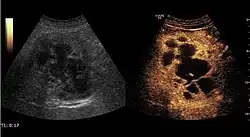

The ultrasound appearance is a well defined lesion, with very thin, almost unapparent walls, without circulatory signal at Doppler or CEUS investigation. The content is transonic suggesting fluid composition. The presence of membranes, abundant sediment or cysts inside is suggestive for parasitic, hydatid nature. Posterior from the lesion the acoustic enhancement phenomenon is seen, which strengthens the suspicion of fluid mass. They typically displace normal liver vessels but no vascular or biliary invasion occurs.

Liver cyst

Hydatid liver cyst. Diagnostic criteria are the presence of membranes and sediment inside.